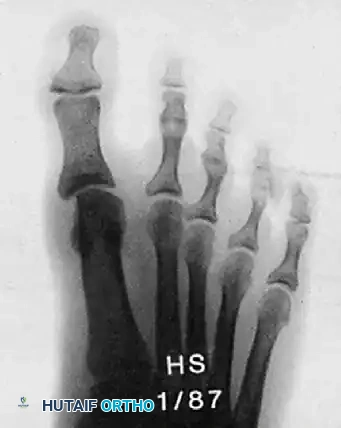

الصور التالية توضح حالة لمريض مراهق يعاني من انحراف شديد، وكيف تم التعامل معها جراحياً ومتابعتها